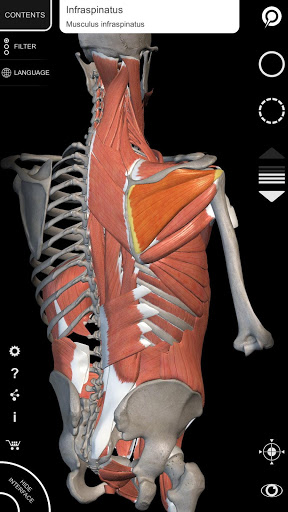

"Anatomy 3D Atlas" memungkinkan Anda mempelajari anatomi manusia dengan cara yang mudah dan interaktif.

Melalui antarmuka yang sederhana dan intuitif, Anda dapat mengamati setiap struktur anatomi dari sudut mana pun.

Model 3D anatomi sangat terperinci dan memiliki tekstur hingga resolusi 4k.

Pembagian berdasarkan wilayah dan tampilan yang telah ditetapkan sebelumnya memudahkan pengamatan dan studi bagian tunggal atau kelompok sistem dan hubungan antara organ yang berbeda.

MODEL ANATOMI 3D

• Sistem muskuloskeletal